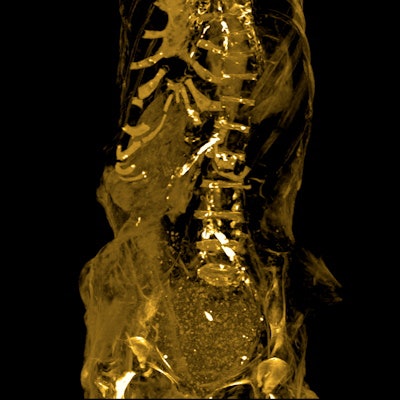

She noted that definite atherosclerotic changes are visible as high-density areas of calcification within the walls of identifiable arteries: right and left carotid bulbs, right and left coronary arteries, abdominal aorta, superior mesenteric artery, coeliac artery, bilateral iliac, femoral and peripheral leg arteries. Also evident was mild lateral curvature of the dorsal spine with its convexity to the left (scoliosis); no structural abnormalities of the spine or anomalous vertebrae could be seen.